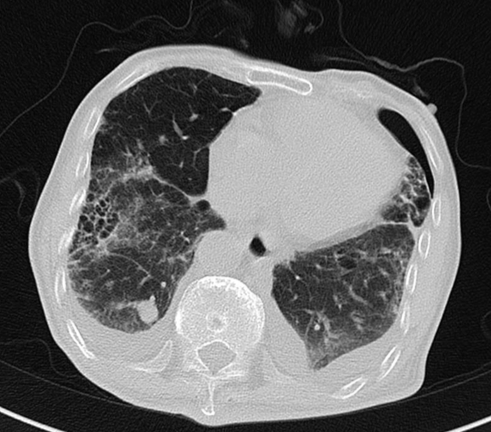

2020-01-08查胸部CT:双肺间质纤维化伴双肺气肿,双肺炎症,伴支气管扩张,右肺上叶结节样影,性质待定,双侧胸腔积液,纵膈多发肿大淋巴结,主动脉及冠状动脉硬化。

△ 2020.01胸部CT

2020-08-31复查胸部CT:右肺结节影,结合病史考虑转移性病变,左侧局限性气胸,双肺气肿,双肺间质性病变,双侧胸腔积液;心脏增大,主动脉硬化。

△ 2020.08胸部CT